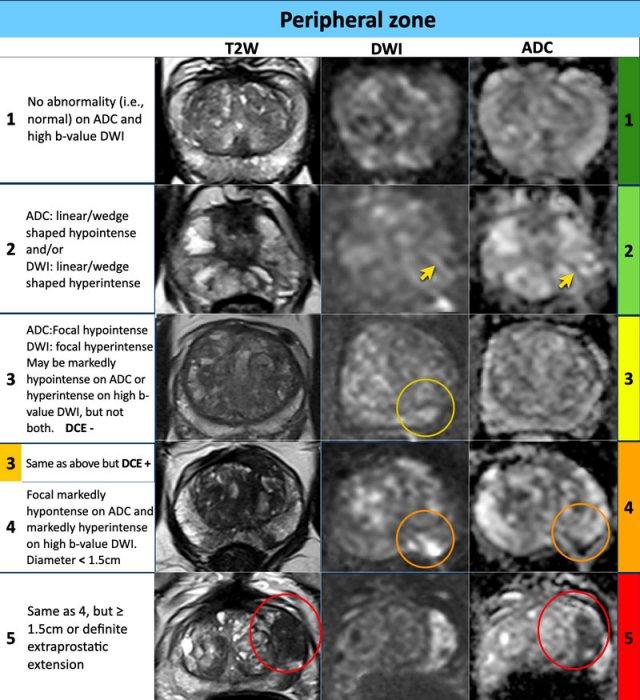

Vùng ngoại vi

PI-RADS

Đối với vùng ngoại vi, chuỗi xung DWI/ADC là chuỗi xung chính để xác định phân loại đánh giá PI-RADS.

Vùng ngoại vi – DWI/ADC mức độ 1

- Không có bất thường nào được phát hiện trên ADC và DWI giá trị b cao.

Vùng ngoại vi – DWI/ADC mức độ 2

- Hình dạng tuyến tính/hình nêm với giảm tín hiệu trên ADC và/hoặc tăng tín hiệu dạng tuyến tính/hình nêm trên DWI giá trị b cao.

Vùng ngoại vi – DWI/ADC mức độ 3

- Giảm tín hiệu khu trú (rõ ràng và khác biệt so với nền) trên ADC và/hoặc tăng tín hiệu khu trú trên DWI giá trị b cao

- Có thể giảm tín hiệu rõ rệt trên ADC hoặc tăng tín hiệu rõ rệt trên DWI giá trị b cao, nhưng không đồng thời cả hai.

- Tổn thương mức độ 3 vẫn được xếp điểm PI-RADS 3 nếu không có ngấm thuốc khu trú (âm tính), nhưng sẽ được nâng lên điểm PI-RADS 4 nếu có ngấm thuốc khu trú.

Vùng ngoại vi – DWI/ADC mức độ 4

- Giảm tín hiệu rõ rệt khu trú trên ADC và tăng tín hiệu rõ rệt trên DWI giá trị b cao

- Kích thước <1,5 cm theo chiều lớn nhất.

Vùng ngoại vi – DWI/ADC mức độ 5

- Tương tự mức độ đánh giá 4 nhưng ≥1,5 cm theo chiều lớn nhất hoặc

- Xâm lấn rõ ràng ra ngoài tuyến tiền liệt (EPE) hoặc có biểu hiện xâm lấn.

Ví dụ về PI-RADS 1-5

Các ví dụ về điểm PI-RADS từ 1-5 được trình bày trong bảng.

Tại vùng ngoại vi, phân loại đánh giá PI-RADS của một tổn thương được xác định chủ yếu dựa trên DWI/ADC và đối chiếu với hình ảnh chuỗi xung T2W và DCE.

Tại vùng ngoại vi, một tổn thương không rõ ràng hoặc không xác định được (mức độ 3) sẽ được xếp vào phân loại PI-RADS 4 nếu DCE dương tính, tức là có ngấm thuốc khu trú hoặc ngấm thuốc sớm hơn.

Tổn thương vẫn được xếp vào phân loại PI-RADS 3 nếu DCE âm tính, tức là không có ngấm thuốc sớm hoặc ngấm thuốc lan tỏa không tương ứng với tổn thương khu trú trên T2W/DWI, hoặc ngấm thuốc khu trú tương ứng với tăng sản lành tính tuyến tiền liệt (BPH).